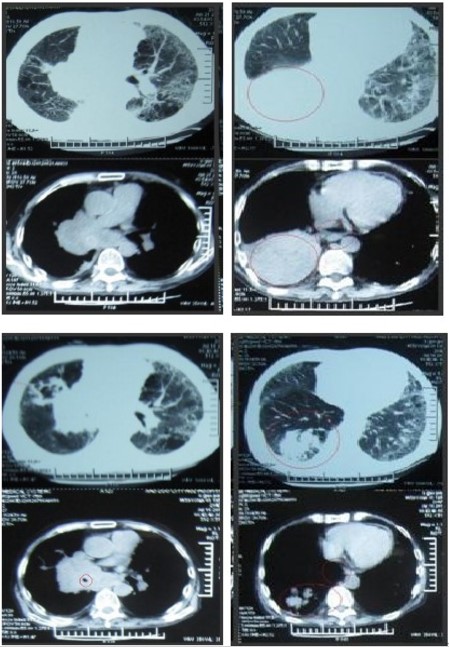

肺癌的CIK细胞治疗效果

治疗前:

右肺门占位伴腰椎转移,右上肺部不张。胸闷、心悸、咳嗽、咯痰、痰中带血、腰痛,无法长时间左立。未行放、化疗,病情进行性加重。

治疗后:

胸闷、腰痛较前逐渐减轻,坐位时间较前延长,治疗后25天复查CT如图所示。